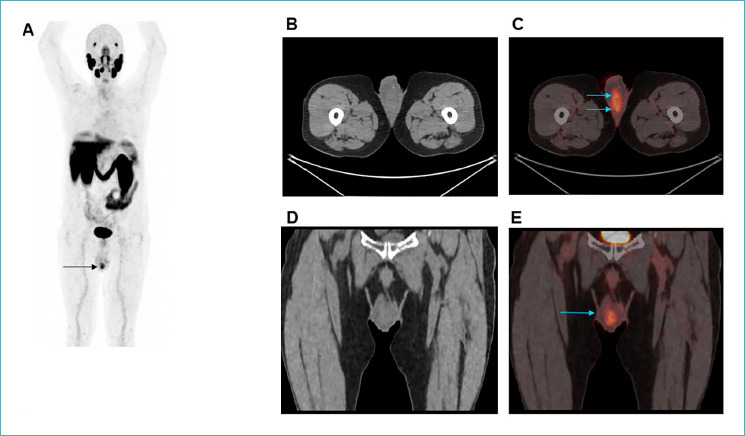

Case presentation: A 70-year-old patient was admitted to the hospital for right scrotal pain. The ultrasound examination described an increase in testicular size, suggesting the possibility of orchiepididymitis. Past medical history reported a previous prostate adenocarcinoma. Inflammatory blood tests were normal. Importantly, PSA was 3.3 ng/ml. PET scan positivity in the scrotum raised suspicion of a relapse. Therefore, he underwent right orchiectomy.